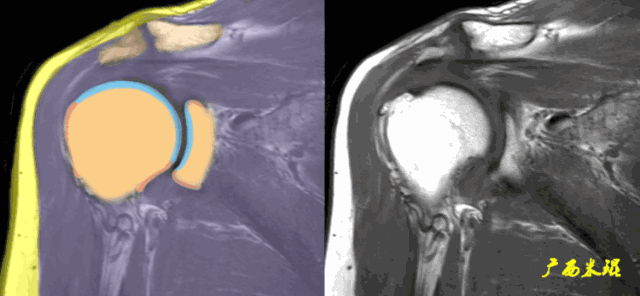

肩关节MRI检查扫描平面

(3)平行于关节盂/垂直于盂肱关节,主要评估盂唇,同时兼顾肩胛下肌、冈下肌及小圆肌。

正常肩袖的MRI表现

各个序列肩袖均表现为均匀的低信号,是肌腱的延续。